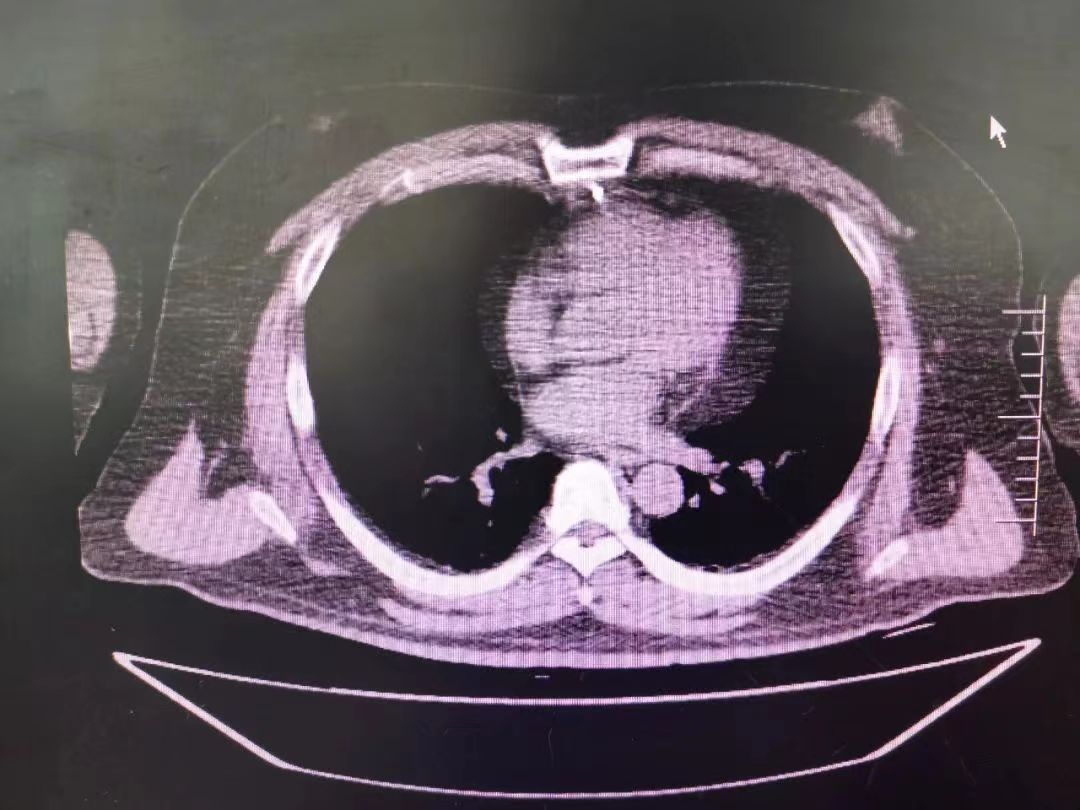

CT室門口,焦燥的家屬不停的走動(dòng)著、等待著,看到醫(yī)生的到來,快速跑到醫(yī)生面前說:“醫(yī)生,快幫我看看,病人怎么樣”。陳醫(yī)生過去一看,一個(gè)體型偏胖的患者平躺在床上,一把剪刀齊根直插胸口觸目驚心,陳醫(yī)生不由眉頭一緊,轉(zhuǎn)身去看電腦CT影像 --剪刀斜著刺入胸骨,將胸骨完全穿透,刀尖距離心包約1-2mm,正下方是主動(dòng)脈,大量心包積液?再一看,患者肥胖,脂肪組織多,不排除脂肪偽影。考慮患者血壓相對平穩(wěn),由于緊張導(dǎo)致心率快,立刻安撫患者,讓其保持安靜,盡量避免咳嗽,避免深呼吸和過多運(yùn)動(dòng)。隨即撥通了武小剛主任的電話:“主任,這有一位患者,銳器刺傷不排除已經(jīng)損傷到心臟,病人目前血壓平穩(wěn)”“嚴(yán)密監(jiān)測患者病情變化,準(zhǔn)備急診手術(shù),我馬上到”武主任說。